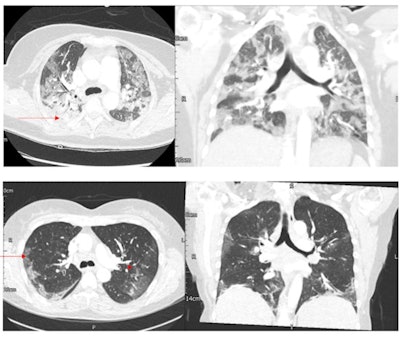

The SARS-CoV-2 omicron variant shows fewer and less severe changes on chest CT than its delta variant predecessor, but it does have at least one distinct manifestation -- bronchial wall thickening, research published June 21 in Radiology has found.

"Bronchial wall thickening was more common with omicron than with delta SARS-CoV-2," the researchers noted.

More of the individuals who contracted the omicron variant had normal results on CT pulmonary angiograms compared with those who had the delta variant, and those ill with omicron had CT severity scores lower by 7.2 points than those ill with delta.

The takeaway? Omicron causes less acute illness and fewer hospitalizations, but it does spread rapidly, and bronchial thickening is more than doubly common in patients with omicron than those with delta (odds ratio, 2.4 and 1, respectively), according to the authors.